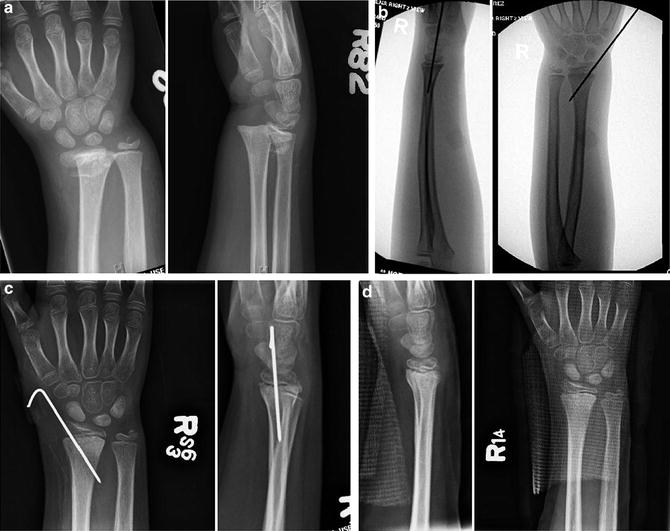

Distal Radius Fracture Wrist Fractures 43 Off The current report is a controlled randomized trial comparing two methods of conservative versus volar plate fixation for the management of drf (type 1 based on fernandez classification of distal radius fractures) plus coronal shift. The compendium of recent clinical and mechanical data suggests that coronal shift should be added to the classic measures of distal radius fracture reduction because of its fundamental role in druj stability.

Pdf Coronal Shift Of Distal Radius Fractures Influence Of The Distal In contrast, the stronger association observed between radial translation and dash scores suggests that coronal plane displacement may play a more substantial role in disability after extra articular distal radius fractures, consistent with emerging evidence highlighting the importance of coronal alignment. Distal radial fractures are the most common adult orthopaedic fracture. we sought to determine whether the incidence of this injury is changing and identify trends in its occurrence. This is clinical trial was conducted on 50 patients with distal radial fracture plus radius coronal shift referred to the kashani hospital affiliated at isfahan university of medical sciences from march 2014 to april 2017. This is a randomized clinical trial conducted on 50 patients with distal radius fracture (type 1 based on fernandez classification of distal radius fractures) with a coronal shift in 2014 17.

Distal Radius Fractures Buyxraysonline This is clinical trial was conducted on 50 patients with distal radial fracture plus radius coronal shift referred to the kashani hospital affiliated at isfahan university of medical sciences from march 2014 to april 2017. This is a randomized clinical trial conducted on 50 patients with distal radius fracture (type 1 based on fernandez classification of distal radius fractures) with a coronal shift in 2014 17. Distal radius fractures are the most common orthopaedic injury and generally result from fall on an outstretched hand. A new radiologic sign for diagnosis of proximal radius convergence during distal radius fracture is presented as well as technical tips for correction of this deformity. Fracture fixation strategies most distal radius fractures treated with locked volar plating. The distal radius literature often appears contradictory because “distal radius fracture” is a broad label applied to many biologically different injuries. trials mix extra articular and complete articular fractures, younger workers and frail retirees, bridging and nonbridging external fixation, and older nonlocking versus modern locking.